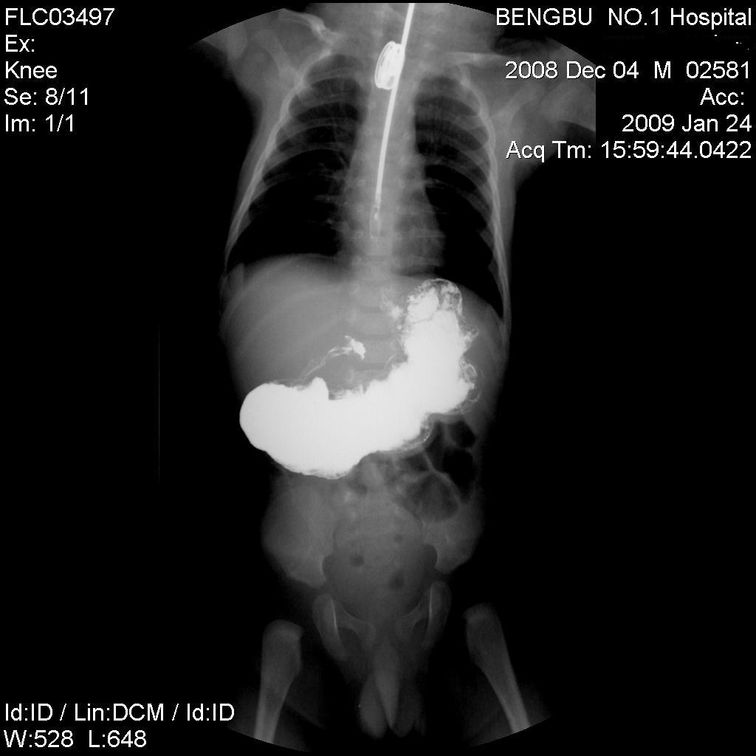

以下是引用余辉在2009-1-25 10:41:00的发言:[br]幽门管显著拉长变细,可见肩样征,支持:考虑先天性肥厚性幽门狭窄

以下是引用黑白光影在2009-1-27 21:35:00的发言:[br]典型先天性肥厚性幽门狭窄。